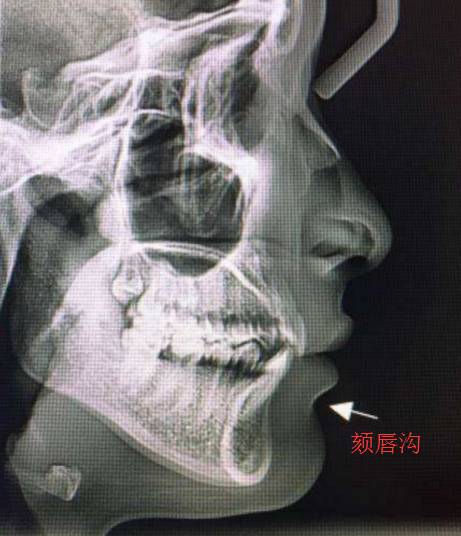

这个地方特别的平,没有唇颏沟。

顺手科普唇颏沟。